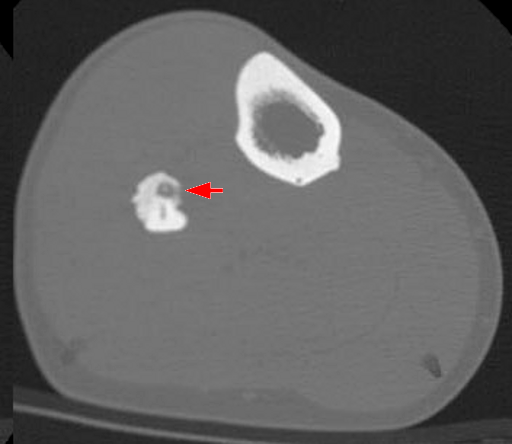

Osteoid Osteoma

Osteoid osteoma is a subtype of osteoma.

In osteoid osteoma, reactive bone forms a ring around a benign tumor of osteoblasts, which produce osteoid.

Osteoid osteoma occurs more commonly in young adults (younger than 25 years of age), and is more common in males.

When osteoid osteoma develops in the cortex of a long bone, such as the femur, it causes bone discomfort that can be managed with aspirin.

Imaging of osteoid osteoma classically reveals a bony mass (< 2.0 cm) with a radiolucent core (osteoid).

The main differential to osteoid osteoma is an osteoblastoma.

Osteoblastomas are similar to osteoid osteomas, however osteoblastomas are larger bigger (> 2.0 cm), may develop in the vertebrae, and manifests as bone pain that is not relieved by aspirin.